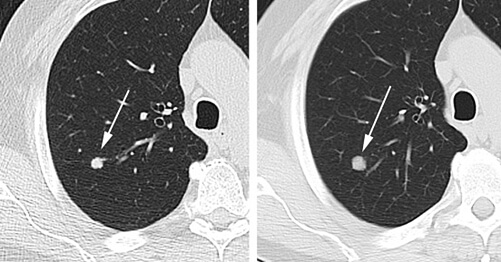

2.3.2. N1

N1은 한쪽 폐에 암이 있으면, 암이 있는 폐 쪽 림프절에만 전이가 된 경우를 말합니다. 좀 더 자세히 말하면 동측 기관지 주변/동측 폐문 림프절/동측 패내 림프절에 전이된 것입니다.

즉, 폐암이 있는 동일 측 림프절에 전이가 된 것으로 이해를 하시면 됩니다. N1까지는 생존율이 높은 것으로 나옵니다.

2.3.3. N2

N2는 N1처럼 같은 동일 측 림프절에 전이가 됐으나, 폐의 종격동과 심장 주변에 있는 림프절로 전이가 된 것 을 말합니다. 이 경우부터는 수술이 힘들고, 수술을 하더라도 어려운 상태가 됩니다.